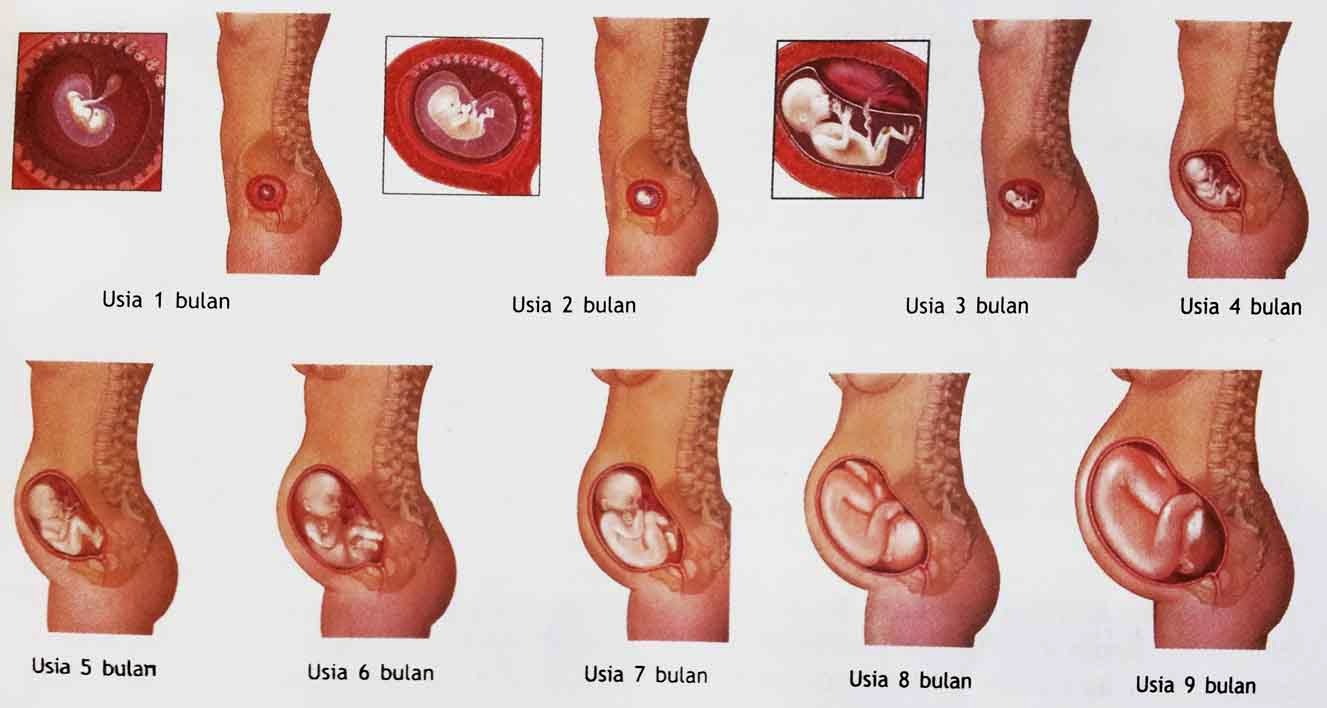

Perkembangan Janin Prakelahiran | army2love’s story

Perkembangan Janin Prakelahiran | army2love’s story

Panduan Lengkap Untuk Ibu Hamil: Perkembangan Janin Dalam Kandungan Ibu Hamil Dari Bulan Ke Bulan

Panduan Lengkap Untuk Ibu Hamil: Perkembangan Janin Dalam Kandungan Ibu Hamil Dari Bulan Ke Bulan

Perkembangan Janin Minggu ke Minggu 1-40 : Gambar Lengkap

Perkembangan Janin Minggu ke Minggu 1-40 : Gambar Lengkap

40 Minggu Tahap Perkembangan Janin di Rahim | Sharing di Sana

40 Minggu Tahap Perkembangan Janin di Rahim | Sharing di Sana

Ini Perkembangan Bayi dalam Kandungan dari Minggu ke Minggu - Alodokter

Ini Perkembangan Bayi dalam Kandungan dari Minggu ke Minggu - Alodokter